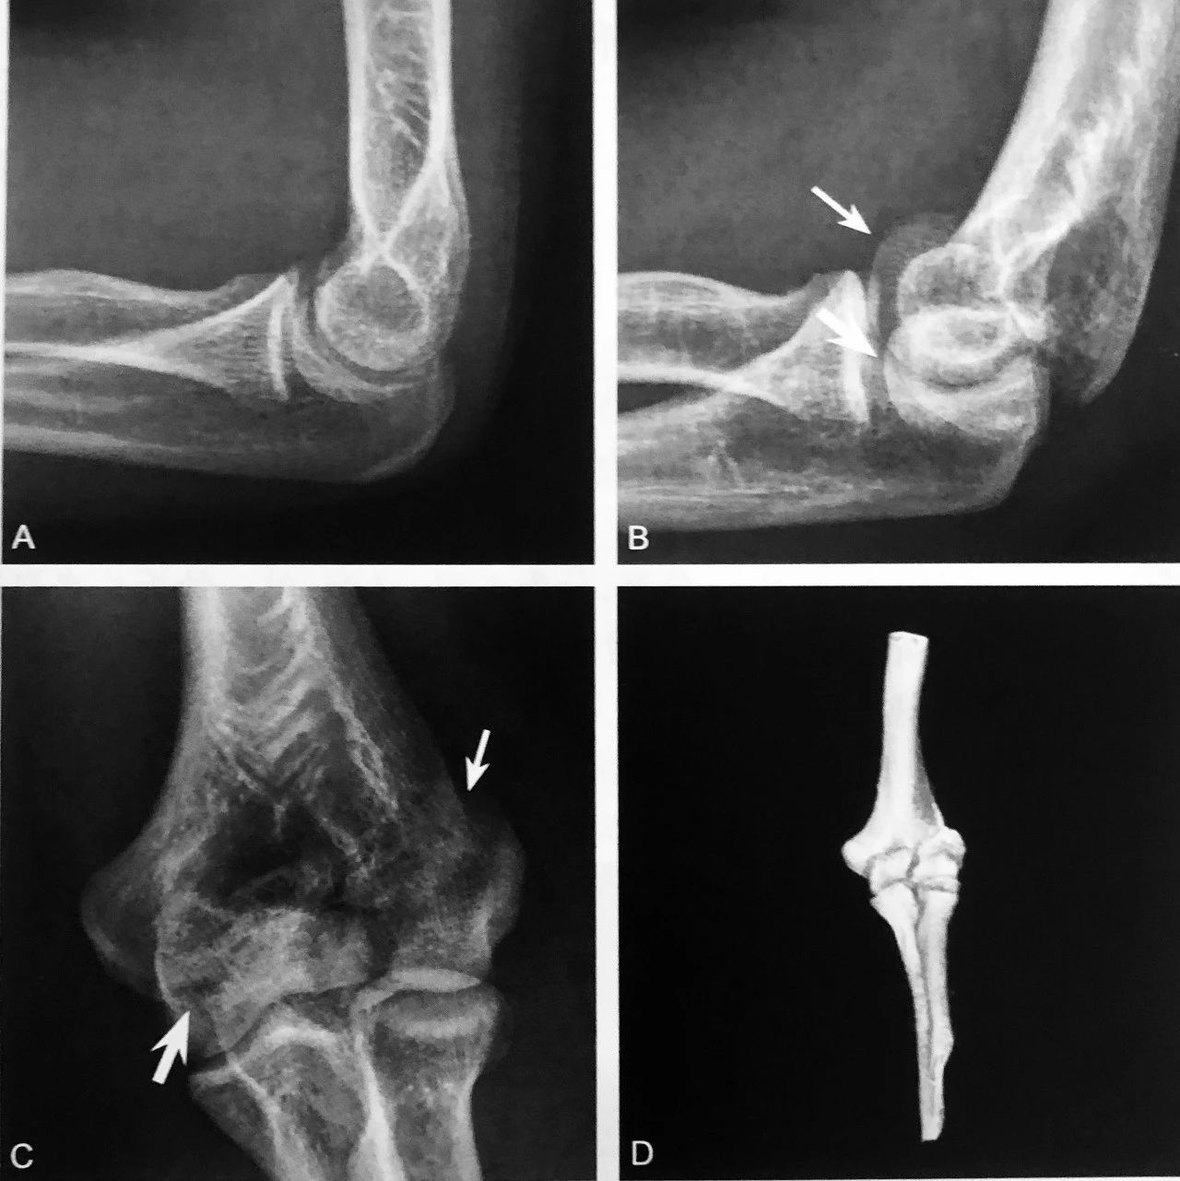

双弧征:A 图正常肘关节侧位 X 线图;B 图患者肘关节 ⅹ 线侧位片示肱骨远端可见两个弧形:一个弧提示肱骨小头游离(细箭头),另一个弧是肱骨滑车游离(粗箭头),双孤征提示肱骨远端冠状面 Dubberley Ⅲ 型骨折;C.同一患者肘关节 Ⅹ 线正位片可见肱骨小头骨皮质不连续(细箭头),肱骨滑车可见线状透亮影(粗箭头);D.CT 的VR 图像可见肱骨远端肱骨小头-滑车骨折

判读要点:

1、肱骨远端冠状面骨折,即肱骨小头-滑车骨折的直接征象;

2、在肘关节侧位片或通过 CT 多平面重建观察;

3、诊断肱骨远端冠状面骨折阳性预测值较高,敏感度相对稍低;4、肱骨小头-滑车骨折应做到手术解剖复位,否则影响预后。